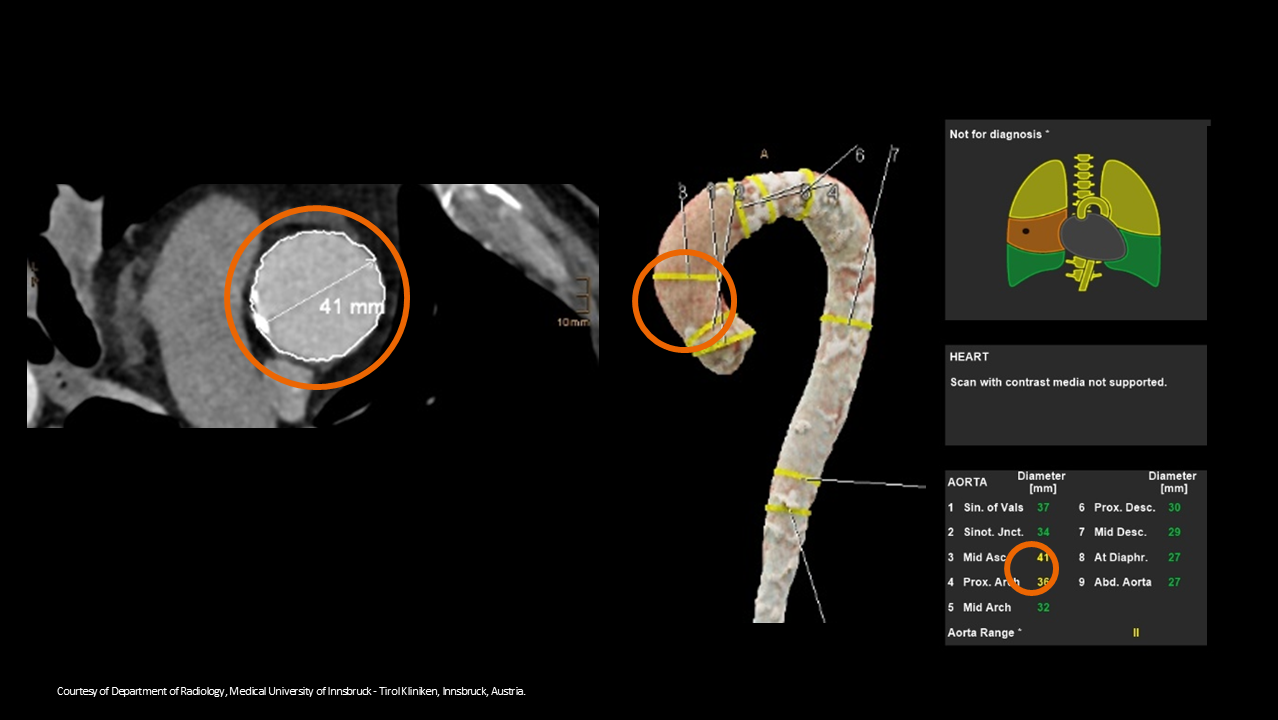

Siemens Healthineers' AI-powered solutions in practice

Discover how Siemens Healthineers' AI-powered solutions are used every day. Watch the video and learn how our technology improves our customers' workflows.